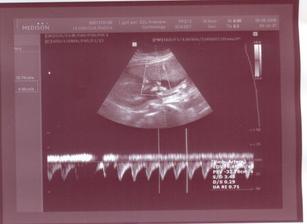

Prvá poradňa bude 2.3.2009. V Poradni všetko OK. UTZ u Dr. Čunderlíka 4.3.2009. Všetko v norme (chvalabohu). Zmenili mi TP zo 4.9.2009 na 13.9.2009. Ďalšia poradňa bude 1.4.2009. V poradni všetko OK. Už len ako dopadnú výsledky z genetiky (7.4.2009). Držte prosím všetci palce. Huráááááááááá AFP testy po opakovaní vyšli super. Konečne budeme mať pokoj. Fuj to bolo dosť zlé ale je to za nami. Už sa len tešiť na bábulko 🙂. Ďalšia poradňa bude 4.5.2009. Snáď uvidíme výbavu 🙂. 25.4.2009 som cítila prvý pohyb (zatiaľ len jeden) 🙂. 29.4.2009 bolo pohybov viacej 🙂)))))). V poradni všetko OK. Asi to bude dievčatko 🙂)))))))))))))))))))))))))). Snáď budem múdrejšia 6.5. 2009 na morfológii. Takže dievčatko to teda nebude 🙂))). Je tam pipík ako hrom. Tešíme sa na Teba synček!!! 20.5.2009 idem na glukózové testy, či nemám tehotenskú cukrovku. Dúfam, že to bude negatívne. Ďalšia poradňa bude 1.6.2009.